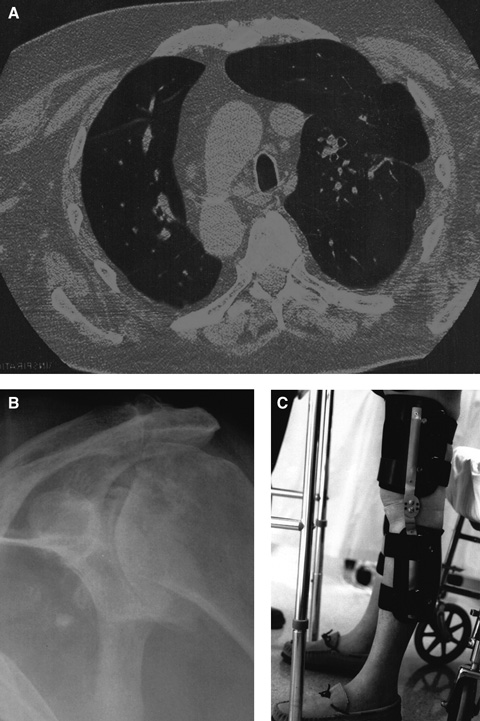

Interstitial pulmonary fibrosis. This group of lung diseases affects the interstitium of the lungs, eventually causing restrictive lung disease. Pulmonary rehabilitation — involving strength and endurance training for arm and leg muscles (eg, walking, cycling, lifting small weights), education on energy conservation and anxiety management, chest physiotherapy, and breathing techniques such as pursed lip and diaphragmatic breathing — has been shown to reduce dyspnoea, improve exercise capacity, enhance quality of life and reduce hospitalisation.9

Chronic shoulder pain from arthritis. This type of pain can be safely and effectively treated by suprascapular nerve block, which avoids the side effects of oral analgesics.10 In our patient, it was an essential component of the rehabilitation program because it enabled him to perform activities of daily living and use a walking frame. Intra-articular steroid injection was not used as it might have worsened the avascular necrosis of the head of the left humerus.

Genu recurvatum. This is an angular deformity (hyperextension at the knee) in the sagittal plane caused by quadriceps weakness. Mediolateral (valgus and varus) instability occurs in the coronal plane. Both deformities require three-point stabilisation. In our patient, orthoses with a free-motion joint and a hyperextension block controlled both deformities and allowed knee movement during walking.11 Gait training with such orthoses includes static weight shift and dynamic balancing exercise in parallel bars, followed by progression to a normal gait pattern.